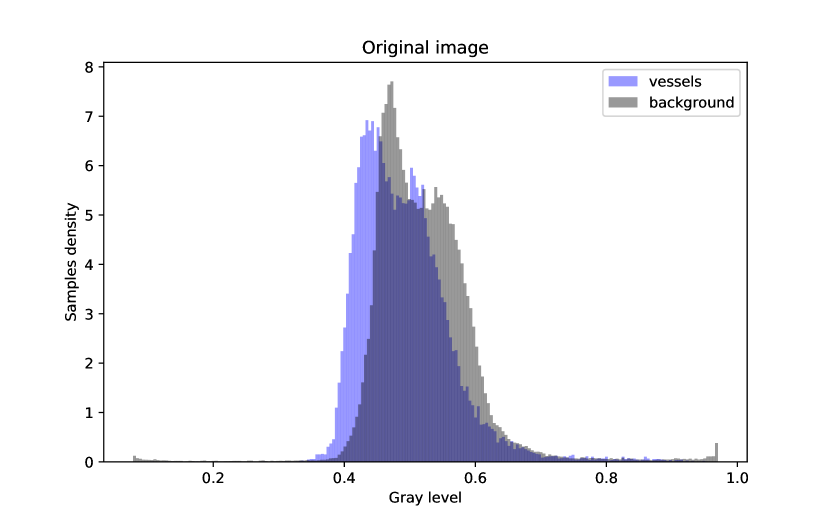

In Figure 4, an example of a retinography before and after applying the preprocessing method is provided, along with the density histograms of vessel pixels and background pixels for each image. The histograms have been computed from the images converted to grayscale.

It can be seen at first glance that the enhanced image, i.e. the one that has been preprocessed, has a greater contrast between the vessels and the background and it presents a more uniform illumination. This enhancement can also be seen in the histograms of the images.